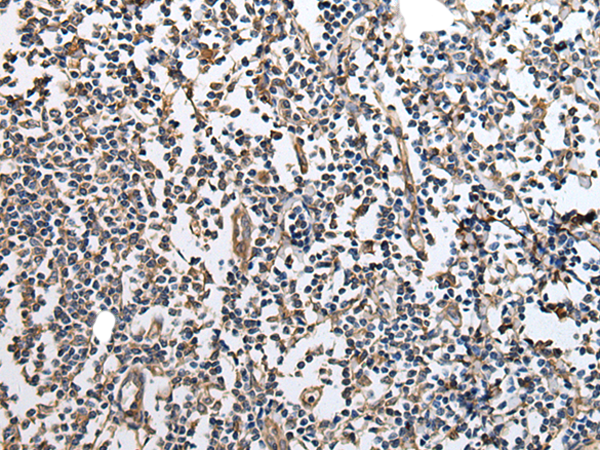

IHC positive control: |

Human lung cancer and human tonsil |